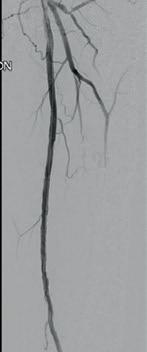

Post-intervention arteriogram

An excellent technical result was achieved. The SFA was widely patent with no significant residual stenosis. The posterior tibial and peroneal arteries were widely patent with brisk flow and no residual stenosis. Significantly improved flow was identified to the foot (Figure 4).